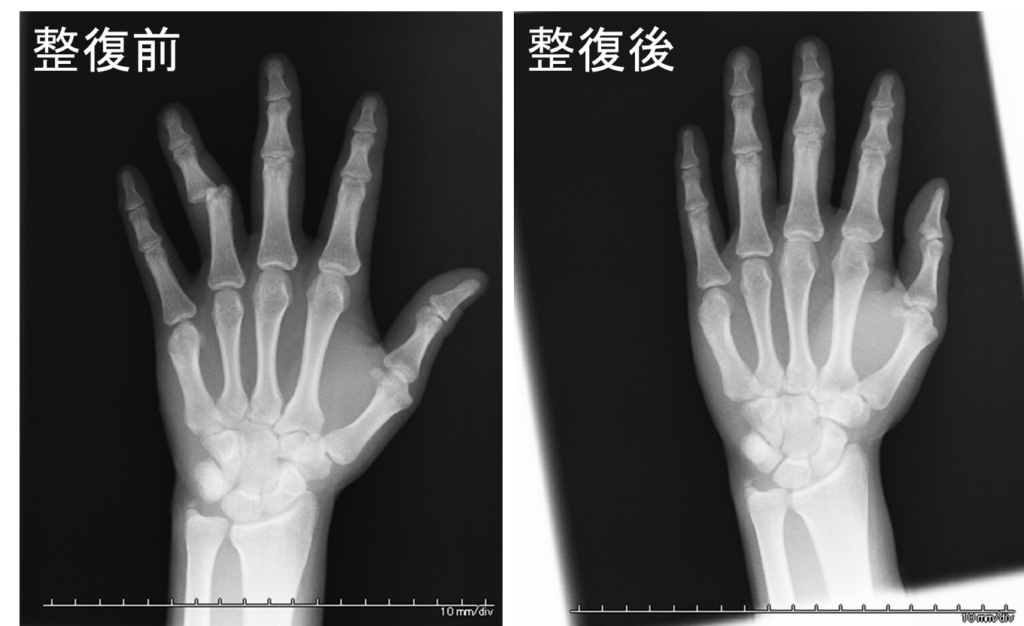

症例2)20歳男子大学生、飲酒時に高椅子から転倒した際に、床に手を衝いて転倒したが、直後は痛みを感じずそのまま帰宅。深夜徐々に痛みが増強し、レントゲン検査の結果、左第4指近位指節間関節不全脱臼、柔道整復を施し処置は見事に成功。1週間ほどの固定後、温熱療法やマッサージで元の機能に戻す治療を行いました。

レントゲンをはじめて見る人には少しショッキングかもしれませんが、